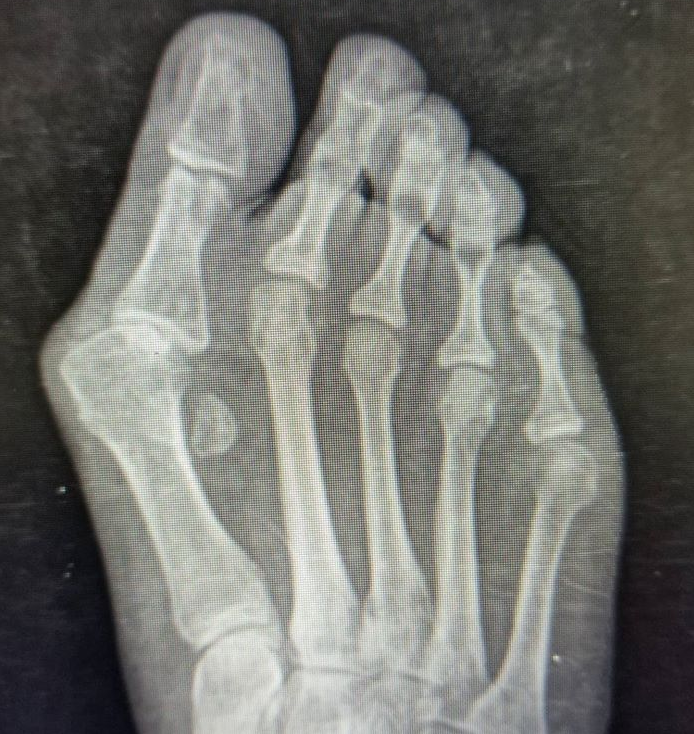

Bunions in 2025: Evidence, Options, and Why Minimally Invasive Lapidus Leads the Pack

Evidence-based bunion care: conservative tips, best shoes & orthotics, and modern minimally invasive Lapidus surgery with early walking recovery